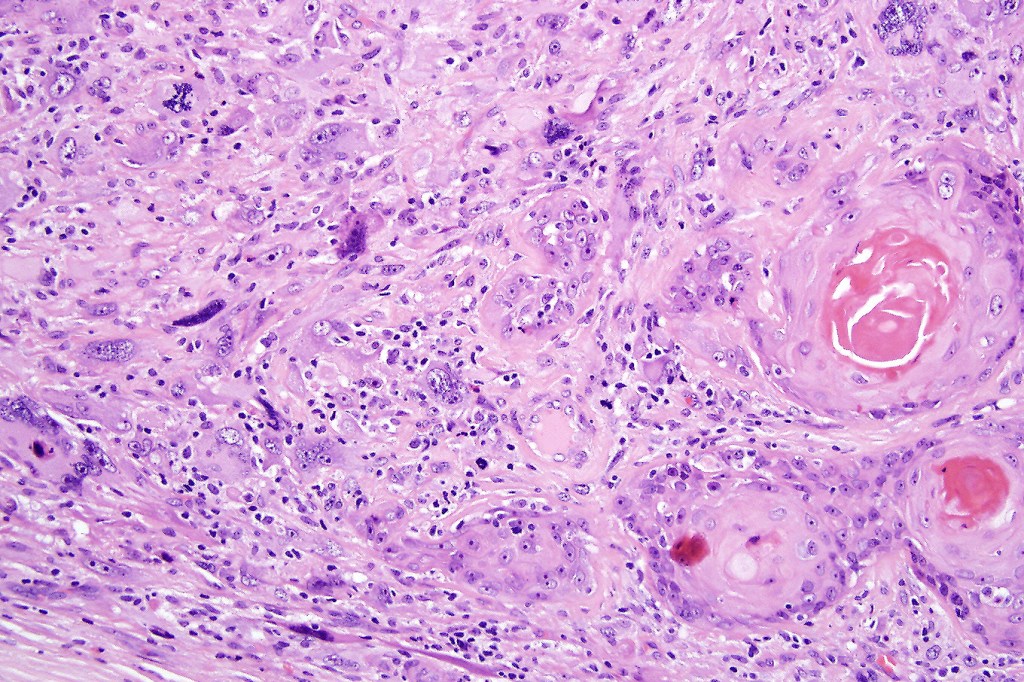

Carcinosarcoma

Cutaneous carcinosarcoma (metaplastic carcinoma, carcinoma with heterologous differentiation)

Histological features

•Osteoid

•Chondroid

•Smooth muscle

•MFH-like features with osteoclasts

•Neural differentiation